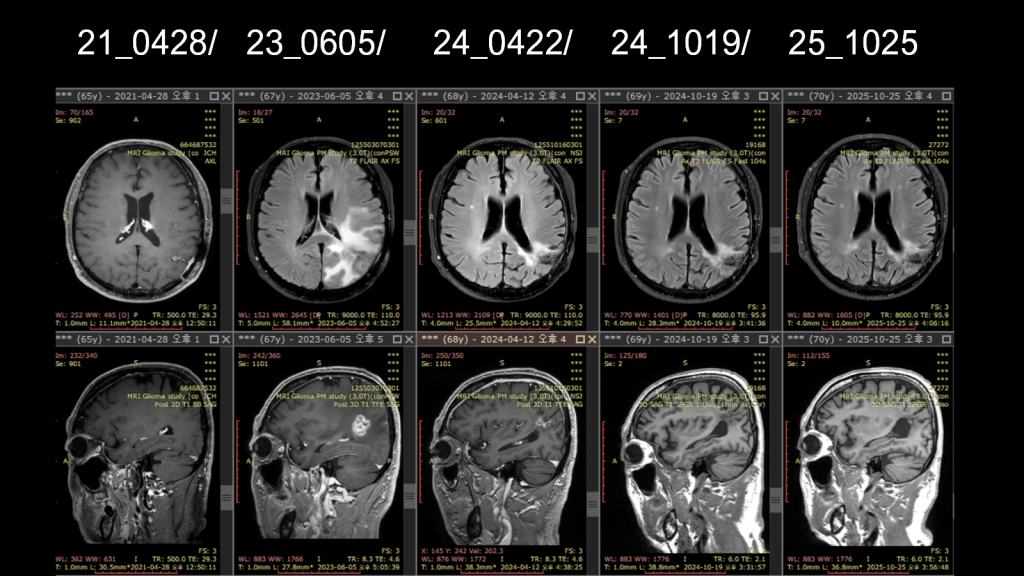

- 2021-04-28: Brain MRI

- About 0.9cm small enhancing nodule in the Lt parietal lobe.–> Equivocal increase

- 좌측 두정엽에 약 0.9cm 크기의 작은 조영 증강 결절. 크기 증가 여부는 불분명함

아래 사진에서 보이듣이 2023년도 6월달사진에는 조영이 굉장히 많이 증가가 되어서 당시 반드시 재발이라고 보고 개두술을 시행하였는데 역시 결과는 단순 염증반응이었고 종양세포는 발견되지 않았다. 조직배양까지 해서 확인하였다고 들었다.

- 2023-06-05: Brain MRI

- More increased size of enhancing nodule… R/o PD (Progressive Disease) > RT change

- 조영 증강 결절의 크기가 더욱 증가함. 치료 변화보다는 질병의 진행(재발) 가능성이 높음

3) 2024년 ~ 2025년: 안정 및 회복기

이기간에는 확연히 줄어드는 소견을 보였고, 환자는 무사히 정년을 마치고 은퇴를 하여 운동과 산을 즐기고 여행을 다니면서 잘 생활하고 있다. 한약은 아직은 1-2 년 더 사용할것을 권유하여 복용하고 있으며

- 2024-04-12: Brain MRI

- Decrease in extent of the irregular enhancing lesion at Lt. parietal lobe

- 좌측 두정엽의 불규칙한 조영 증강 병변 범위 감소

- 2024-10-19: Brain MRI

- Further decrease in extent of the irregular enhancing lesion

- 조영 증강 병변 범위의 추가적인 감소

- 2025-10-25: Brain MRI (최신 기록)

- No newly visible measurable enhancement. NC (No Change) in extent of the irregular enhancing lesion

- 새롭게 나타난 측정 가능한 조영 증강 없음. 기존 병변 부위의 범위 변화 없이 안정적으로 유지됨

경과 요약: 환자분은 2021년과 2023년에 영상검사상 병변의 크기가 증가하여 재발이 의심되었으나, 두 차례의 조직검사를 통해 모두 재발이 아닌 치료(방사선) 관련 변화임이 증명되었고. 2024년 이후부터는 병변이 지속적으로 감소하거나 안정된 상태(NED)를 아주 잘 유지하고 있다. 그리고 지끔까지 정상생활을 하고 있다.